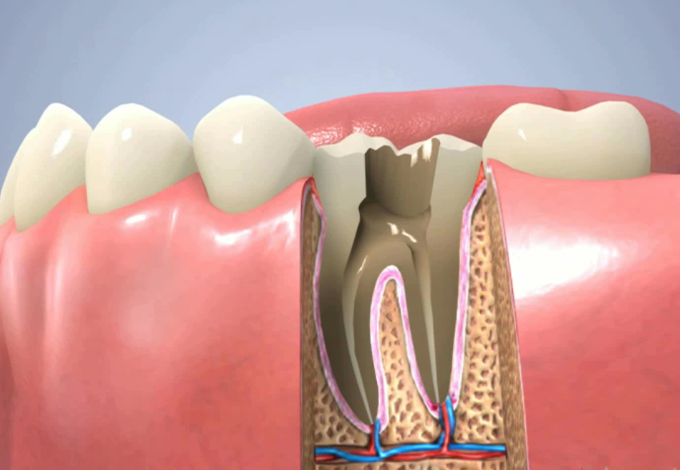

消毒と根管の清掃を数回行い根尖の炎症がだいぶおさまってきました。

でもまだまだです。

炎症がなくなりました!

次は根管充填です。

垂直加圧根管充填で根尖までゴム製の樹脂を詰めます。

根の先まできっちり詰めるので痛みが伴います。レントゲン撮影をしてきちんと根管充填ができているか確認します。